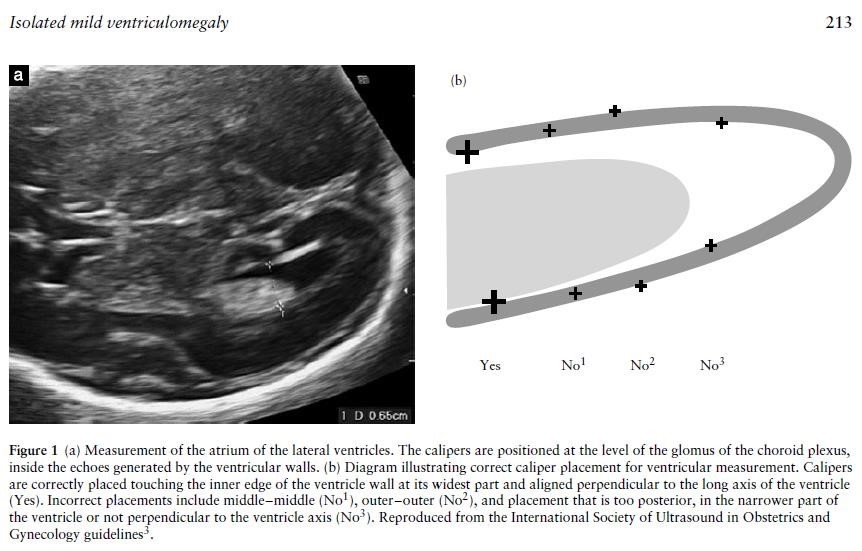

Accurate measurement of the ventricles is important in both defining ventriculomegaly and also assessing progression. The fetal head should be scanned in the axial plane at the level of the frontal horns and the cavum septum pellucidum (CSP) (the same level at which a head circumference is taken), at an appropriate magnification that the head fills the screen. The callipers should be placed at the internal margins of the atrial walls at the level of the parietal occipital groove and the glomus of the choroid plexus, perpendicular to the axis of the ventricle.